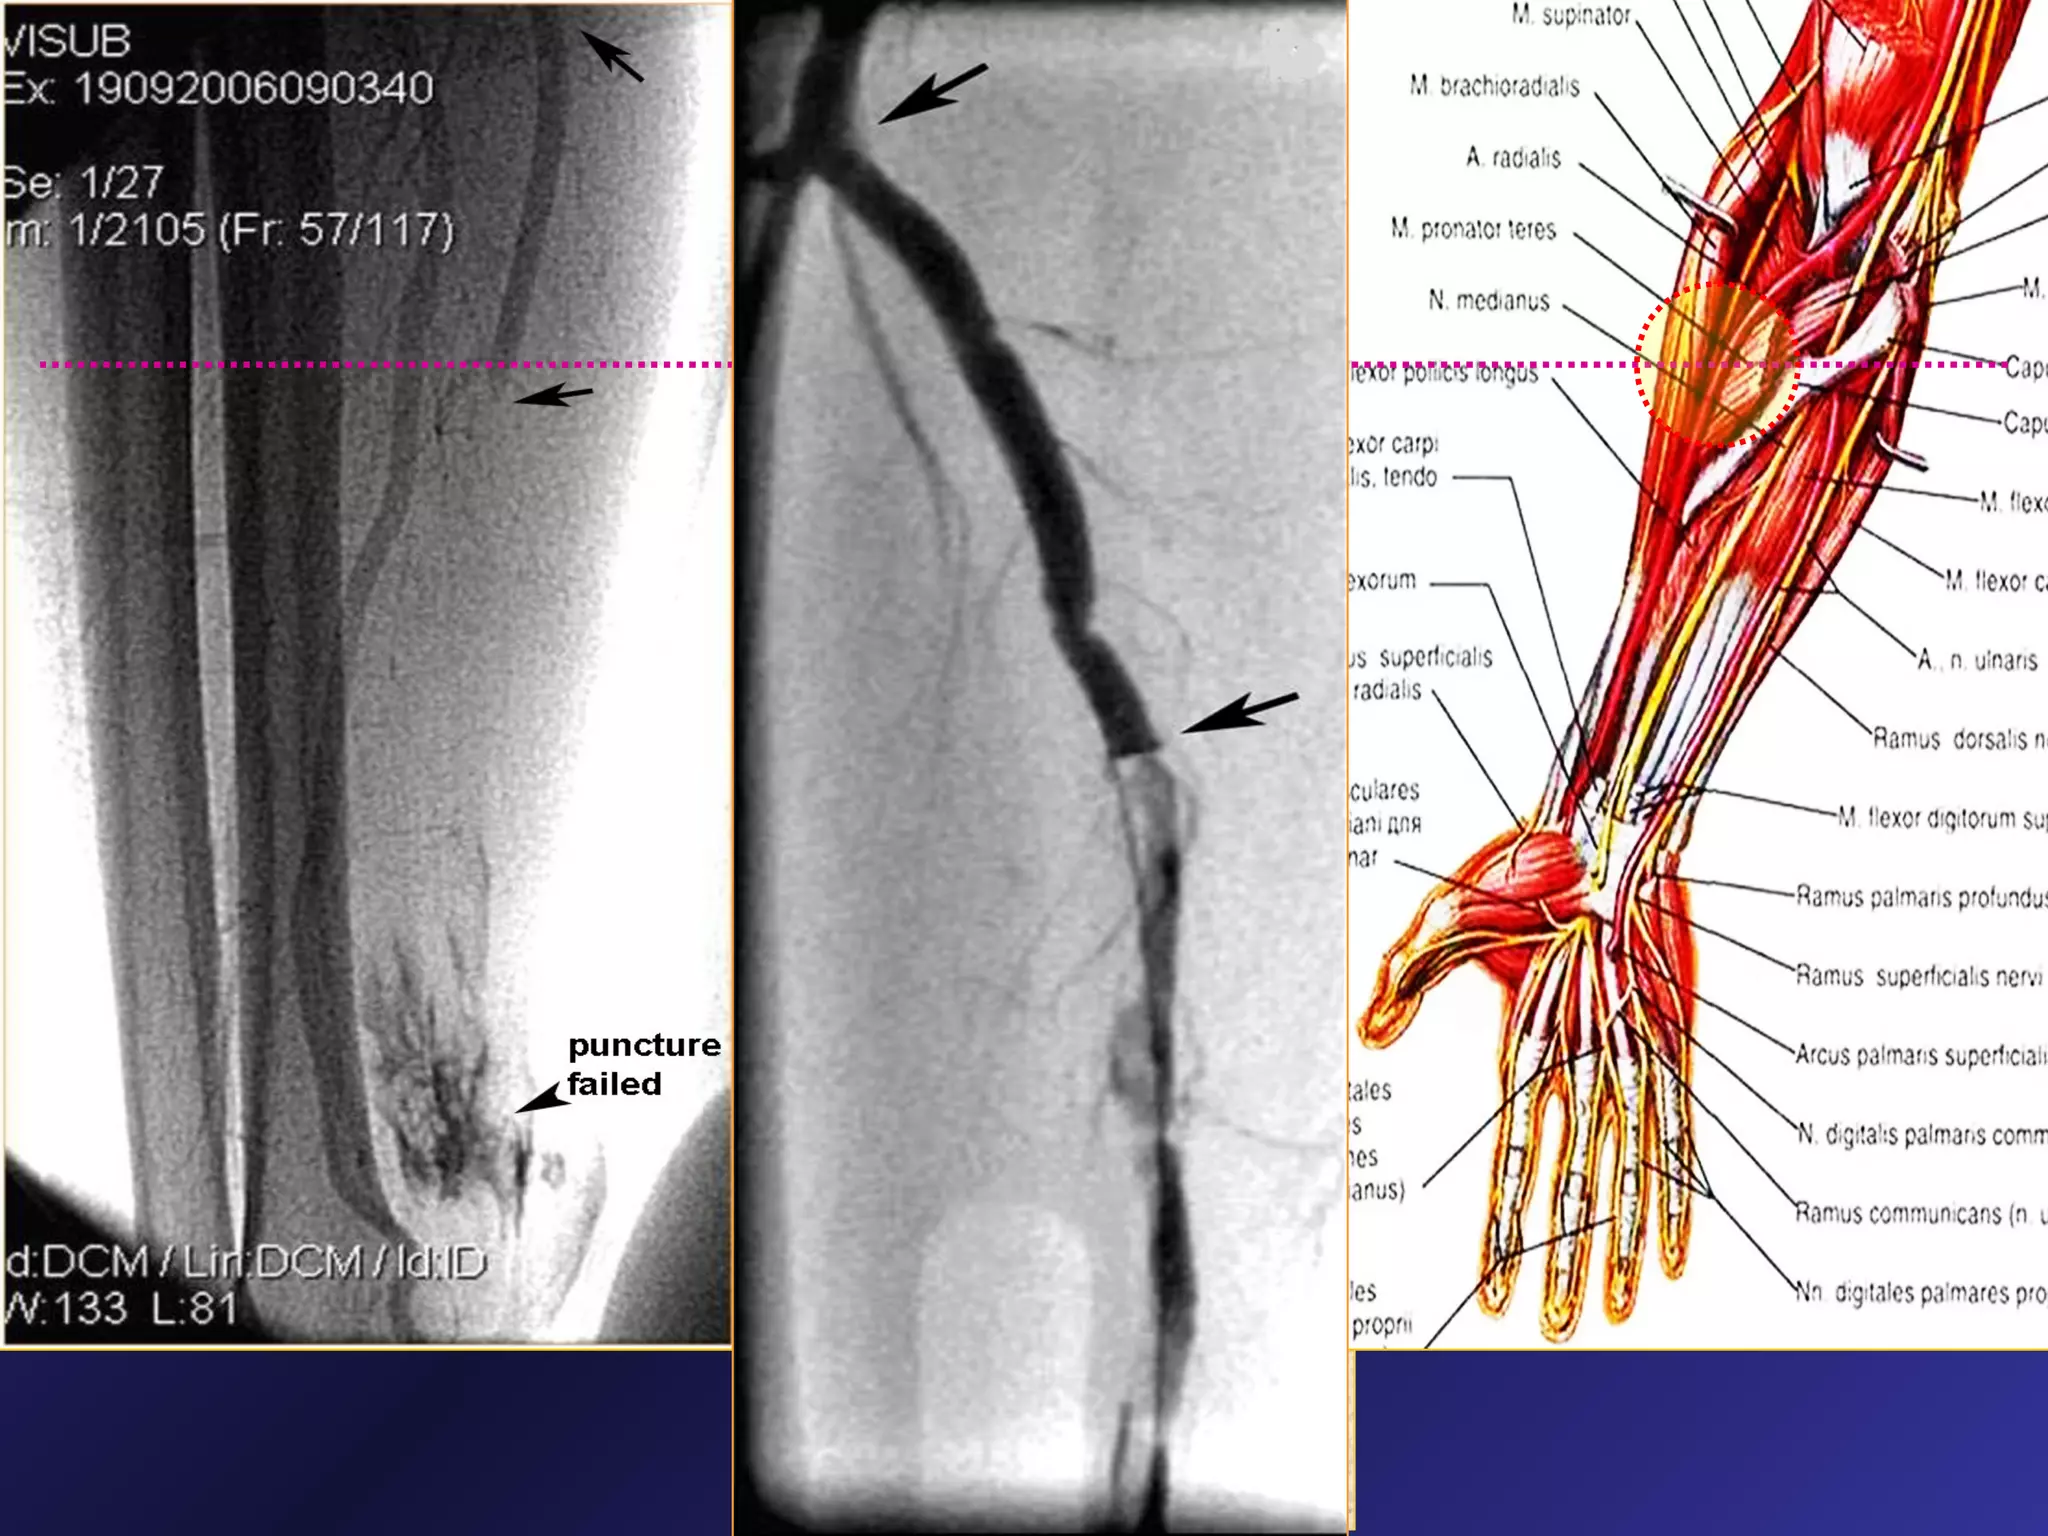

Proximal (“high”) puncture of

occluded radial artery

Proximal Radial artery puncture under US guidance

Bifurcation point

Previous Puncture site

Proximal RA puncture and 7F sheath inserted before PCI

Proximal puncture of high take-off Radial artery

► “High” puncture sucessfully performed in 5

patients (3 –control angio, 2 – PCI);

► in one case proximal punction was performed in

RA with high take-off from brachial artery;

► Only one small haematoma (< 5X5cm) was occured

► Proximal RA catheterization under US control is feasible and safe in

certain case of retrograde recanalization failure.